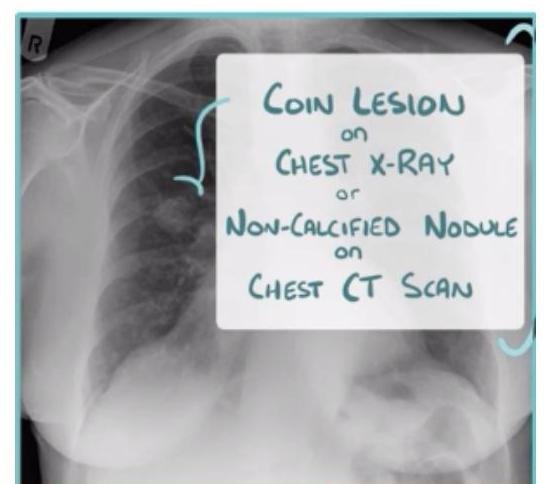

# CÁNCER DE PULMÓN ## DEFINICIÓN Se considera el tipo **Células No Pequeñas** el **cáncer de pulmón** más frecuente; este es una **neoplasia maligna** originada en el **epitelio** que recubre el **aparato respiratorio** (bronquios, bronquiolos y alvéolos) y representa el 80 % de todos los casos de cáncer de pulmón. La OMS divide el cáncer de pulmón en dos clases basadas en su biología, tratamiento y pronóstico: ## 1. CÁNCER PULMONAR DE CÉLULAS NO PEQUEÑAS a. No ESCAMOSO (Adenocarcinoma, Carcinoma de Células Grandes) b. Escamoso (EPIDERMOIDE) 2. CÁNCER PULMONAR DE CÉLULAS PEQUEÑAS ## CÁNCER PULMONAR MÁS COMÚN: ADENOCARCINOMA ## EPIDEMIOLOGÍA - Es la primera causa de muerte en el mundo (hombres) y segunda de mujeres. - Alrededor del 18-25% de muertes en todos los cánceres. - Tumor más letal - Tasa de letalidad: 84 % - Más frecuente en hombres. - Variantes según estatus socioeconómico (tipo de cigarrillos, exposición laboral o agentes inhalados). ## FACTORES DE RIESGO: - Tabaquismo activo: 85% - Tabaquismo pasivo: 5% - ÍNDICE TABÁQUICO >20 PAQUETES/AÑO - Radón - Asbesto - Radiación - Níquel - Cromo Factores que influyen en el tabaquismo: - Duración del tabaquismo - Número de cigarrillos - Inicio a edad más temprana - Predisposición genética TABAQUISMO TOTAL: 95% ÍNDICE TABÁQUICO Número de cigarrillos/día x Número de años que lleva fumando 20 ## Tabaquismo pasivo: - Riesgo relativo: 1.24 - Causante del 25-30% de los cánceres de pulmón en no fumadores. - 30 % de la población general está expuesta al humo pasivo. - Vivir con un fumador: Incrementa el riesgo 30% de cáncer pulmonar. # DETECCIÓN Y TAMIZAJE Se recomienda el uso de un protocolo basado en tomografías de tórax de baja dosis anual como herramienta de detección oportuna en pacientes con: 1. Índice tabáquico igual o mayor a 30 cajetillas/año 2. Edad 55-74 años Incorporar programas de deshabituación al tabaquismo para disminuir el costo-efectividad y mejorar los programas de detección oportuna. Las características clínicas y radiológicas no pueden distinguir entre nódulos benignos y malignos, aunque es importante estimar la probabilidad clínica de malignidad antes de indicar estudio de imagen: ## PROBABILIDAD MALIGNA BAJA (<5 %) Nódulo sólido indeterminado +8 mm con los siguientes factores: - Paciente joven - Bajo consumo de tabaco - Nódulo de tamaño pequeño - Localización no superior - Resolución completa o casi completa - Disminución progresiva o persistente - Sin crecimiento en los últimos 2 años (en nódulos sólidos) - Sin crecimiento en los últimos 3-5 años (en nódulos subsólidos) ## PROBABILIDAD MALIGNA ALTA (+65 %) Nódulo sólido indeterminado +8 mm con los siguientes factores: - Edad avanzada - Alto consumo de tabaco - Historia de cáncer previa - Nódulo de gran tamaño - Nódulo con márgenes irregulares - Localización en lóbulos superiores - Evidencia de crecimiento en estudios de imagen # CLÍNICA Es un cuadro insidioso que no produce síntomas hasta que la enfermedad está avanzada. En aproximadamente el 10 % de los casos, el cáncer pulmonar se diagnostica en pacientes asintomáticos cuando se realiza una radiografía (Rx) de tórax por otro motivo. ## SIGNOS Y SÍNTOMAS MÁS FRECUENTES 1. Tos (8-75 %) 2. Dolor torácico (20-49 %) 3. Disnea (3-60 %) 4. Hemoptisis (6-35 %) 5. Astenia (0-10 %) 6. Pérdida de peso (0-68 %) 7. Anorexia (0-20 %) 8. Acropaquia (0-20 %) 9. Fiebre (0-20 %) ## Al diagnóstico: - 20 % enfermedad aislada - 25 % metástasis regionales - 55 % metástasis a distancia ## SÍNDROMES PARANEOPLÁSICOS ## TUMOR DE PANCOAST Es un tumor del surco superior (región apical torácica) que afecta la estructura de la pared torácica apical a nivel de la primera costilla superior, pero no necesariamente tiene un síndrome de Horner o dolor irradiado hacia el brazo; presenta dolor de hombro. Frecuentemente invade el plexo braquial, vasos subclavios o médula. - Asociado a síndrome de Horner: ptosis + miosis + anhidrosis ## METABÓLICOS  - Hipercalcemia: asociada a metástasis óseas, asociada a producción ectópica de hormona paratiroidea. - Síndrome de Cushing: producción excesiva de corticotropina, con exceso de producción de cortisol que causa debilidad muscular, pérdida de peso, hipertensión, hiperglucemia e hipocalemia severa. - común en cáncer de células pequeñas.  # DIAGNÓSTICO Para un diagnóstico preciso y estadificación se requiere un abordaje completo con el fin de evaluar la extensión de la enfermedad y realizar lo siguiente: General: Historia clínica, exploración física, evaluación de comorbilidades y capacidad funcional. ## Imagen: - Radiografía de tórax: se recomienda en todas las sospechas de cáncer pulmonar. - Si hay nódulo sospechoso (+8 mm) \rightarrow TAC de alta resolución. - TAC helicoidal de tórax: se recomienda contrastada y de abdomen ante la sospecha, independientemente de la radiografía (Rx). - Tomografía por emisión de positrones (PET-CT): importante marcador diagnóstico y de planificación del tratamiento (Tx). - RMN: recomendada para evaluación quirúrgica de los estadios T4 N1. Laboratorio: BH, función renal, enzimas hepáticas y metabolismo óseo. Función cardiopulmonar: EKG, espirometría, capacidad de difusión pulmonar de monóxido de carbono. Obtención de tejido: broncoscopia, USG endoscópico bronquial, biopsia guiada por TAC.   PATRÓN metastásico con imagen en "suelta de globos", con apariencia algodonosa. # TOMA DE BIOPSIA ## CITOLOGÍA DE ESPUTO - Método útil para diagnóstico y no invasivo. - Ante un resultado negativo, se deberá continuar con otras pruebas. - Sensibilidad variable dependiendo del tumor y del procesamiento. ## BRONCOSCOPIA - Es la prueba recomendada para obtener una muestra diagnóstica por biopsia de cualquier lesión visible. - El uso de técnicas avanzadas (USG endobronquial) debe considerarse en tumores donde los métodos tradicionales han fallado para la obtención de material. ## BIOPSIA POR ASPIRACIÓN CON AGUJA FINA GUIADA POR USG - Es la primera elección para el diagnóstico patológico en nódulos sospechosos. ## MEDIASTINOSCOPIA - Es la prueba con el valor predictivo negativo más alto para descartar enfermedad en ganglios. - No es necesaria en estadios clínicos tempranos IA, sin crecimiento ganglionar y en caso de que el PET-CT no muestre captación ganglionar mediastínica. - Se indicará si las pruebas menos invasivas no son accesibles, valorables o insatisfactorias. # CÁNCER PULMONAR DE CÉLULAS NO PEQUEÑAS ## CARCINOMA ESCAMOSO (EPIDERMOIDE) - Localización: CENTRAL - Asociado al tabaco. Liberación de hormona paratiroidea  TUMORES CARCINOIDES / CARCINOMA DE CÉLULAS GRANDES  PUEDEN CRECER EN CUALQUIER PARTE DEL PARÉNQUIMA. # TRATAMIENTO ## Etapa clínica I - Resección quirúrgica - Adyuvancia con QT si hay factores de riesgo - Si N+ - radioterapia ## Etapa clínica II y III - Quimiorradioterapia - Inmunoterapia ## Etapa clínica IV - Tratamiento sistémico - Quimioterapia (base de platino) - Terapia dirigida - Inmunoterapia - Metástasis única en SNC - radioqx - Metástasis única en SNC - radioterapia, radioqx